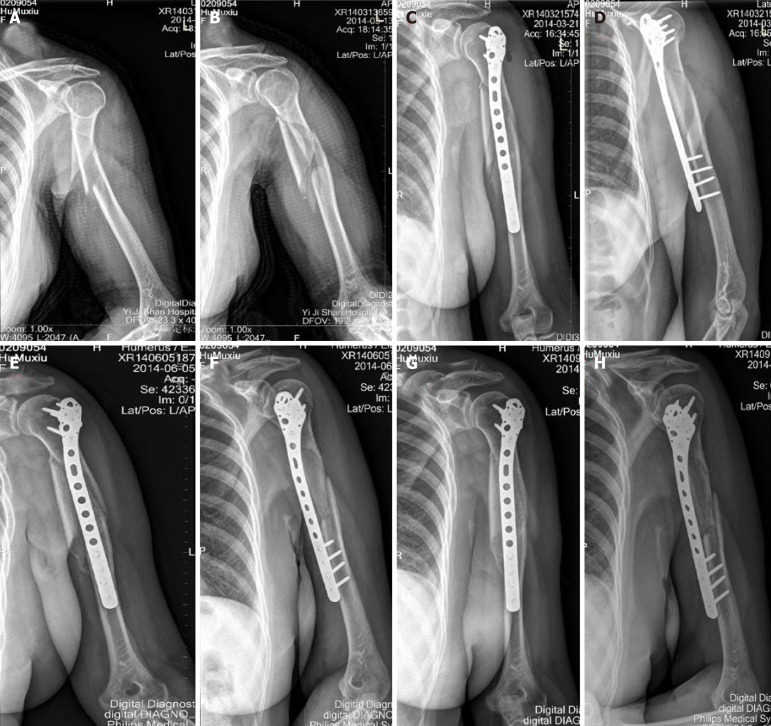

Background: The objective of this study was to evaluate the use of combined parallax-free panoramic X-ray imaging during surgery by enabling the mobile C-arm with minimally invasive plate osteosynthesis (MIPO) in the management of proximal humeral shaft fractures.

Methods: A retrospective series of 17 proximal humeral shaft fractures were treated using combined parallax-free panoramic X-ray imaging during surgery by enabling the mobile C-arm with MIPO. The operating time and radiation exposure time were recorded, and early postoperative physical therapy and partial weight bearing were encouraged. Patients were followed at regular intervals and evaluated radiographically and clinically.

Results: The mean operating time and radiation time were 73 (range, 49-95) minutes and 57 (range: 36-98) seconds, respectively. No complications occurred during the operation. All fractures healed at an average of 16.9 (range: 15-23) weeks. The average Constant-Murley score for all the patients was 89.5 (range: 75-100) points. None of the patients showed symptoms of vascular or nerve damage or wound infection. Three months after the operation, none of the patients developed subacromial impingement syndrome. No loosening or fracture of the implants occurred. The frontal and lateral radiographs showed good alignment.

Conclusion: We consider that MIPO with combined parallax-free panoramic X-ray imaging during surgery is an efficient method for treating proximal humeral shaft fractures, and could significantly reduce operative morbidity as well as lower the rate of intra- and postoperative complications.